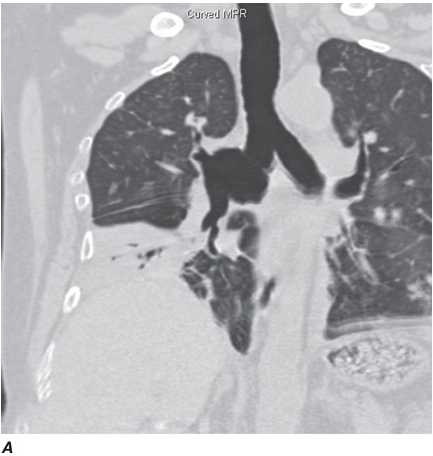

Computed tomography (CT) offers several advantages over routine chest radiography (Figs. C-1A, B and C-2A, B). First, the use of cross-sectional images allows distinction between densities that would be superimposed on plain radiographs. Second, CT is far better than routine radiographic studies at characterizing tissue density, distinguishing subtle density differences between adjacent structures, and providing accurate size assessment of lesions.

CT is particularly valuable in assessing hilar and mediastinal disease (which is often poorly characterized by plain radiography), in identifying and characterizing disease adjacent to the chest wall or spine (including pleural disease), and in identifying areas of fat density or calcification in pulmonary nodules (Figs. C-2A, B). Its utility in the assessment of mediastinal disease has made CT an important tool in the staging of lung cancer, as an assessment of tumor involvement of mediastinal lymph nodes is critical to proper staging. With the additional use of contrast material, CT also makes it possible to distinguish vascular from nonvascular structures, which is particularly important in distinguishing lymph nodes and masses from vascular structures primarily in the mediastinum, and vascular disorders such as pulmonary embolism.

Helical CT Scanning

Recent advances in computer processing have allowed the development of helical CT scanning. Helical CT technology results in faster scans with improved contrast enhancement and thinner collimation. The image is obtained during a single breath-holding maneuver that allows less motion artifact. In addition, helical CT scanning allows the collection of continuous data over a larger volume of lung than is possible with conventional CT. Data from the imaging procedure can be reconstructed as images in planes other than the traditional cross-sectional (axial) view, including coronal, or sagittal planes (Fig. C-3A). Finally, sophisticated volumetric “3D” representations of structures can be produced (Fig. C-3B) including the ability to perform a virtual bronchoscopy, mimicking direct visualization through a bronchoscope (Fig. C-4).